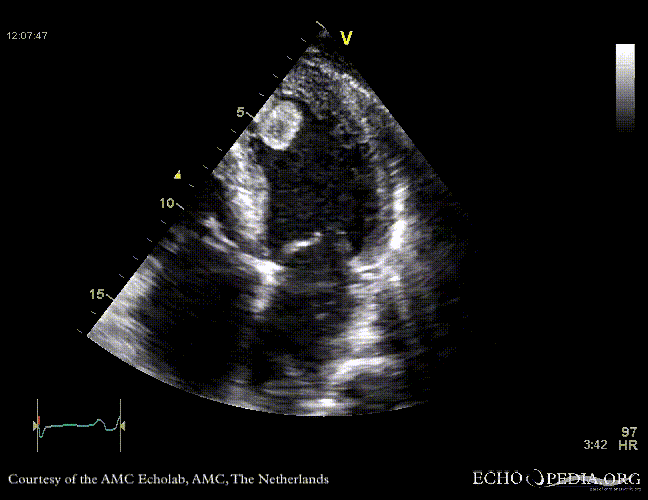

Thrombus in the left ventricle

J. Vleugels, AMC, The Netherlands